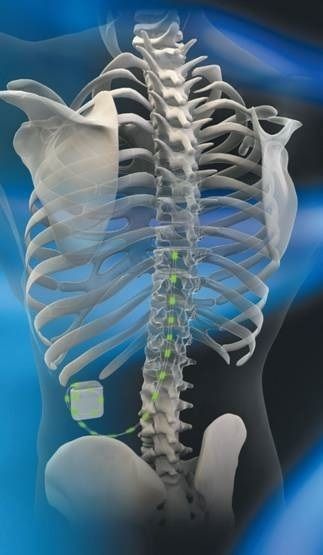

- Implantation of spinal cord electrodes with a neurostimulator (spinal cord stimulation).

Spinal cord neurostimulator placement diagram for chronic pain